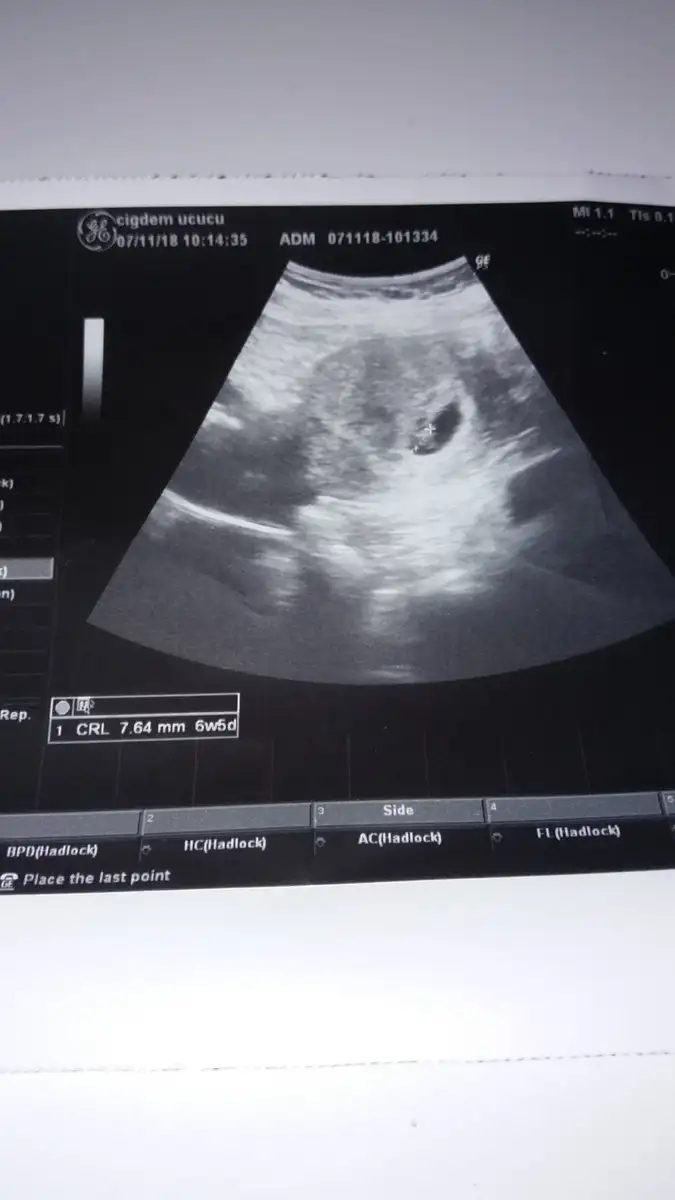

Bana da bakar mısınız tam 8+0 karından bakıldı

Canim baska ilk utrasyon res yokmuBana da bakar mısınız tam 8+0

Maalesef bu ilk ve tekCanim baska ilk utrasyon res yokmu

Bu birz buyuk ama olsun bi tahminde bulunmmi istersen erkege benzetdimMaalesef bu ilk ve tek

Aslinda suan 7+6 oldum ama doktora gittigimde 6+5ti canim kalp atisini duyduk o gun 2 gun geriden gelyodu snada masaallahh canim 9 haftalik olmussun heraldeKaç haftalik canım maşallah bebeğine

Sağlıklı büyüsünlerde geriden gelsede farketmez canim 8+4 ümAslinda suan 7+6 oldum ama doktora gittigimde 6+5ti canim kalp atisini duyduk o gun 2 gun geriden gelyodu snada masaallahh canim 9 haftalik olmussun heralde